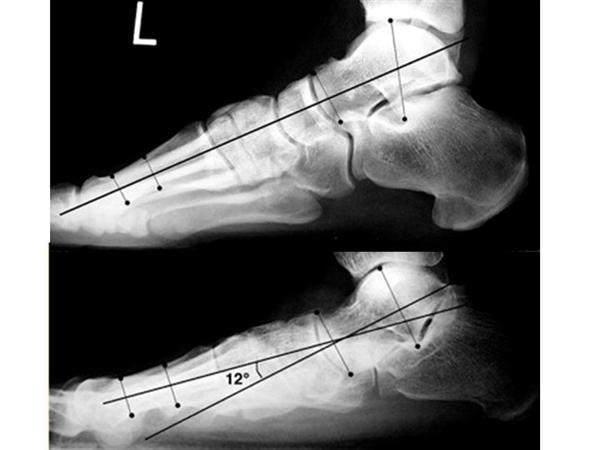

What measurement is this?

Which pic is abnormal?

Mearys angle

(angle subtended from a line drawn through axis of the talus and axis of 1st ray)

Bottom is abnormal - apex plantar therefore flatfoot